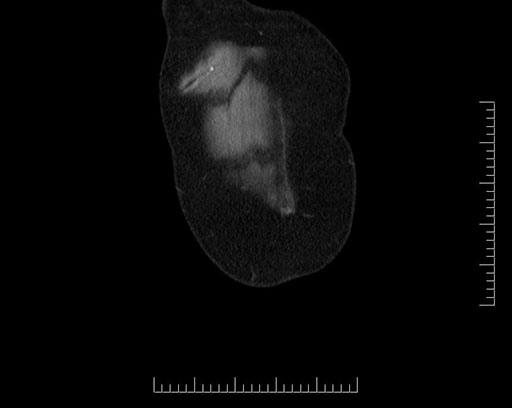

Imaging Analysis

Look through the patient's CT scan to identify any areas of concern for the necessary procedure.

Based on your CT findings, which issue(s) would give reason for "planned slowing down moment(s)" in this case?